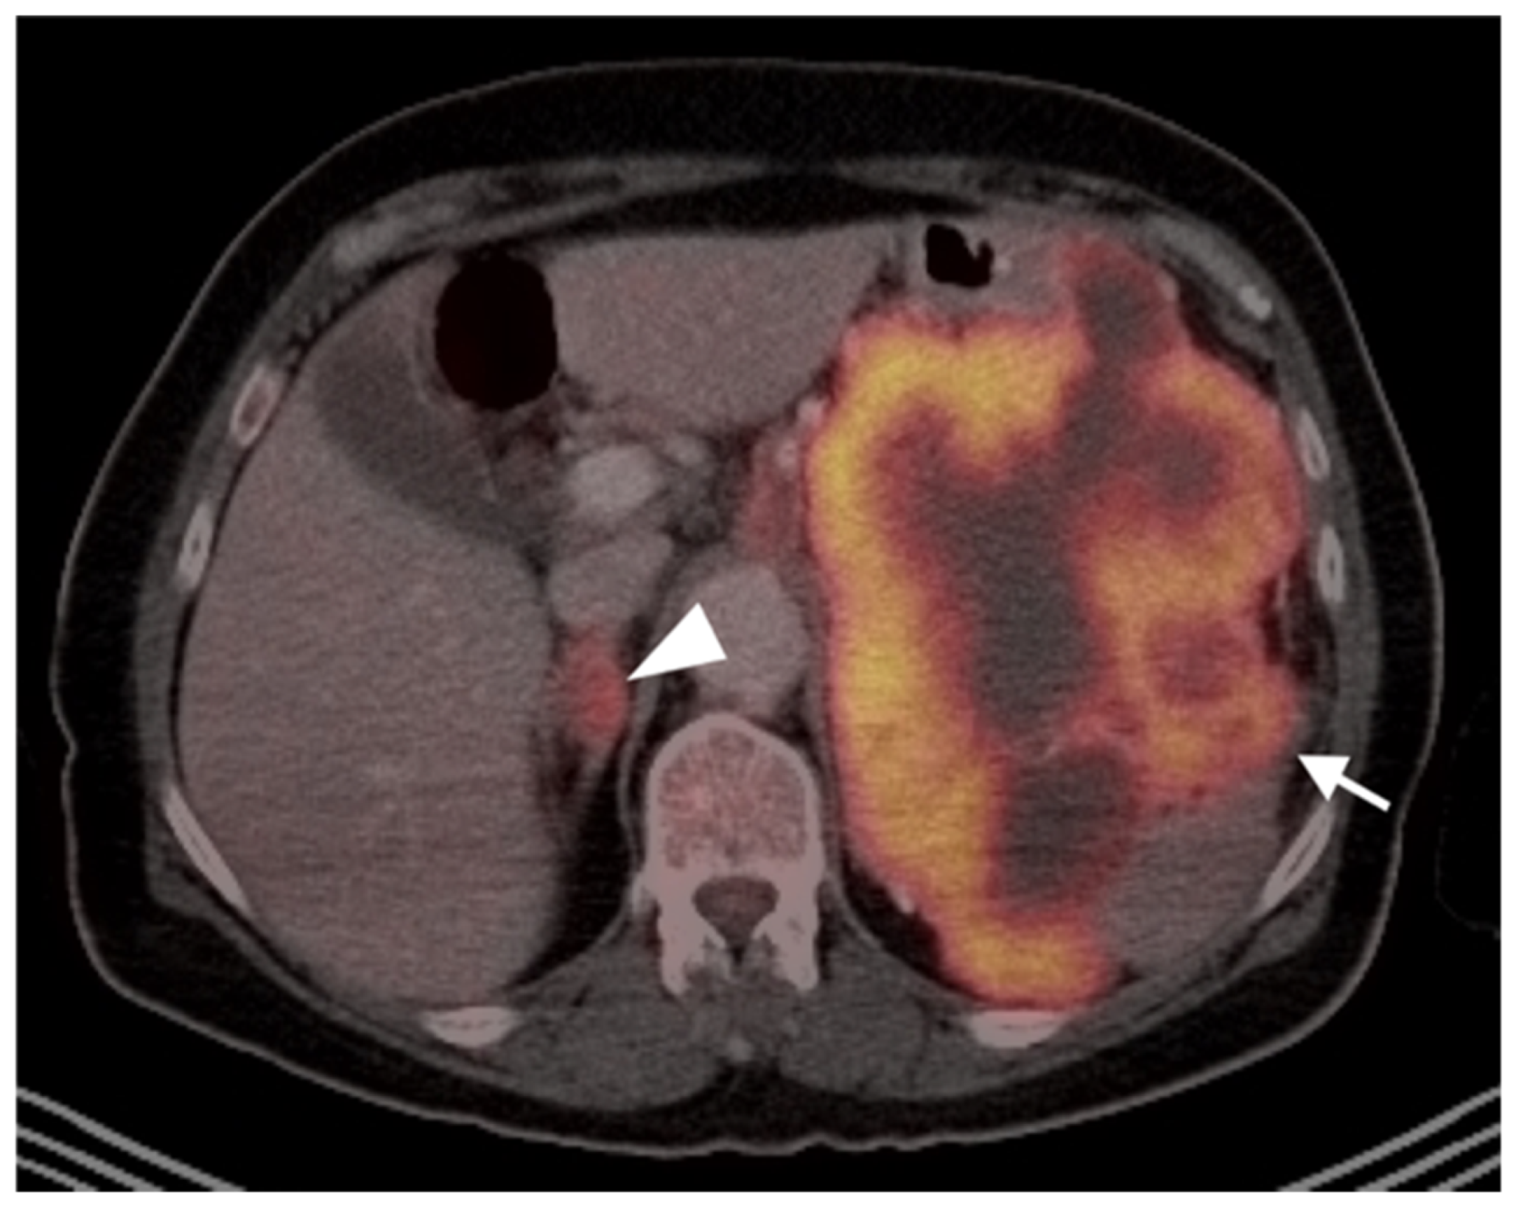

3.1.6. Liposarcoma